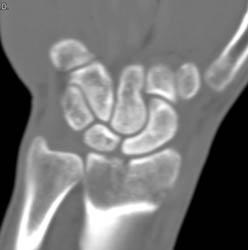

Scaphoid Fracture